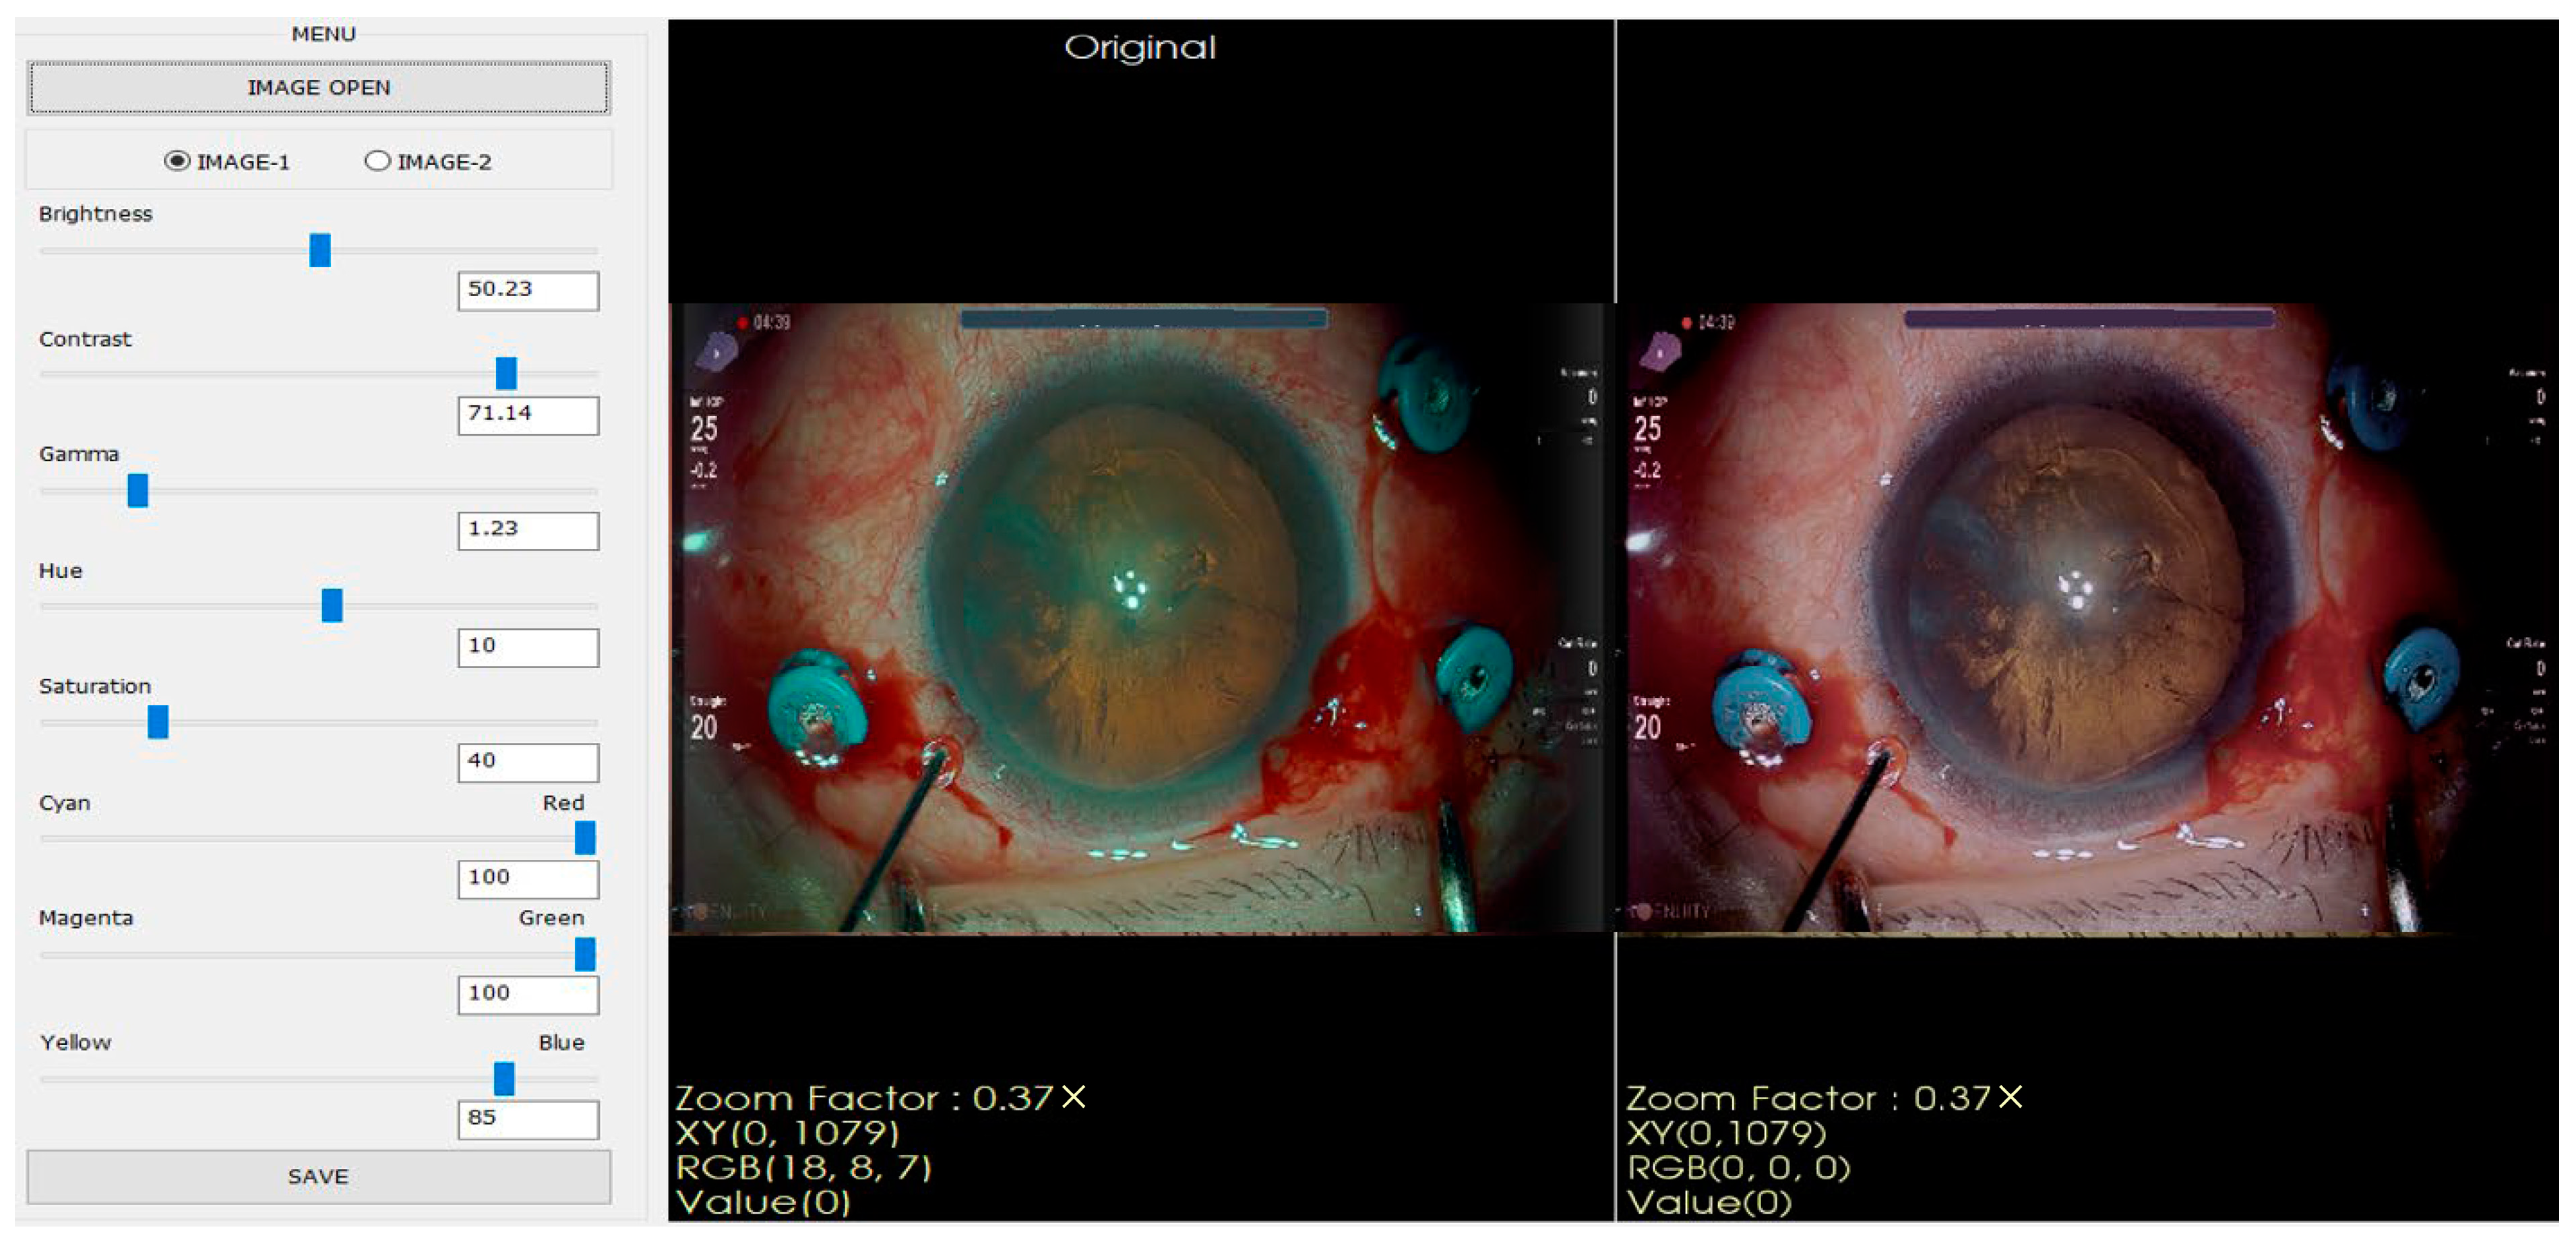

From these images, ophthalmologists recorded eight control parameters: brightness, saturation, contrast, cyan, gamma, magenta, hue, and yellow, enabling the realization of an optimal visual configuration for highlighting the retinal areas by manually adjusting the microscope, as shown in Figure 2.

Figure 2.

The leftmost panel contains scroll bars to adjust the eight parameters, and the two photos positioned in the middle and the right display an unprocessed image and a manually optimized image, respectively.